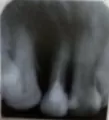

Вчера была у стоматолога, сделали снимок. Врач сказал, что пломбы на снимке хорошие, каналы запломбированы хорошо, ровно. Но, видит на кончике корня маленькое как будто воспаление. Сказал, что это может быть из-за простуды. Лечить не нужно, дал направление в физ.кабинет.